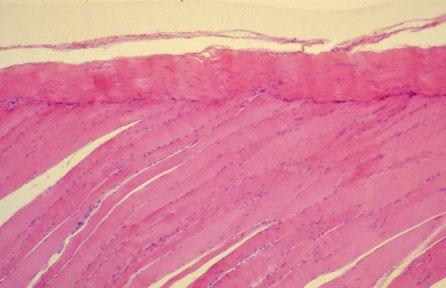

V-62 (4) Slide 15, Muscle-Tendon Junction (H&E). Muscle cells (bottom) have euchromatic and elongated nuclei. Fibrocyte nuclei of tendon (top) are thin and slender, and heterochromatic.